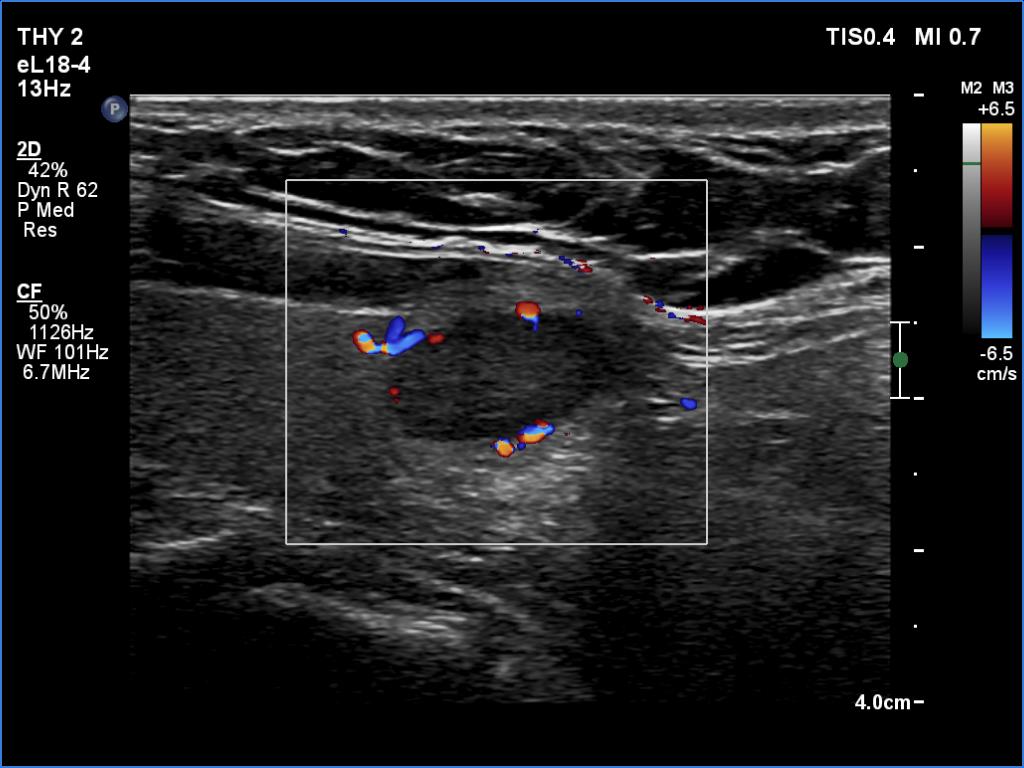

Ultrasonography. The thyroid was echonormal. There was a moderately hypoechoic lesion in the lower pole of the right lobe. The lesion presented no suspicious findings.